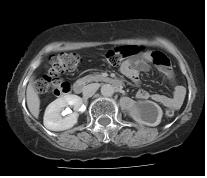

전산화단층촬영은 신우암과 신세포암의 감별에 도움이 되며, 주변 장기로의 침범 여부나 림프선 혹은 원격 장기로의 전이 여부 등을 판단하는데 도움을 줍니다.

[ 전산화단층촬영 ]